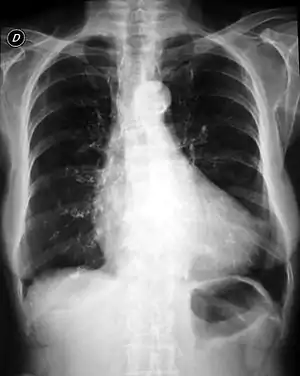

| Cardiomegaly (x-ray)- one of the characteristics of Cantu syndrome | |

The main features of this condition are hypertrichosis, osteochondrodysplasia, and cardiomegaly. There is also a characteristic facies. Other features include patent ductus arteriosus, congenital hypertrophy of the left ventricle, and pericardial effusions.[2]